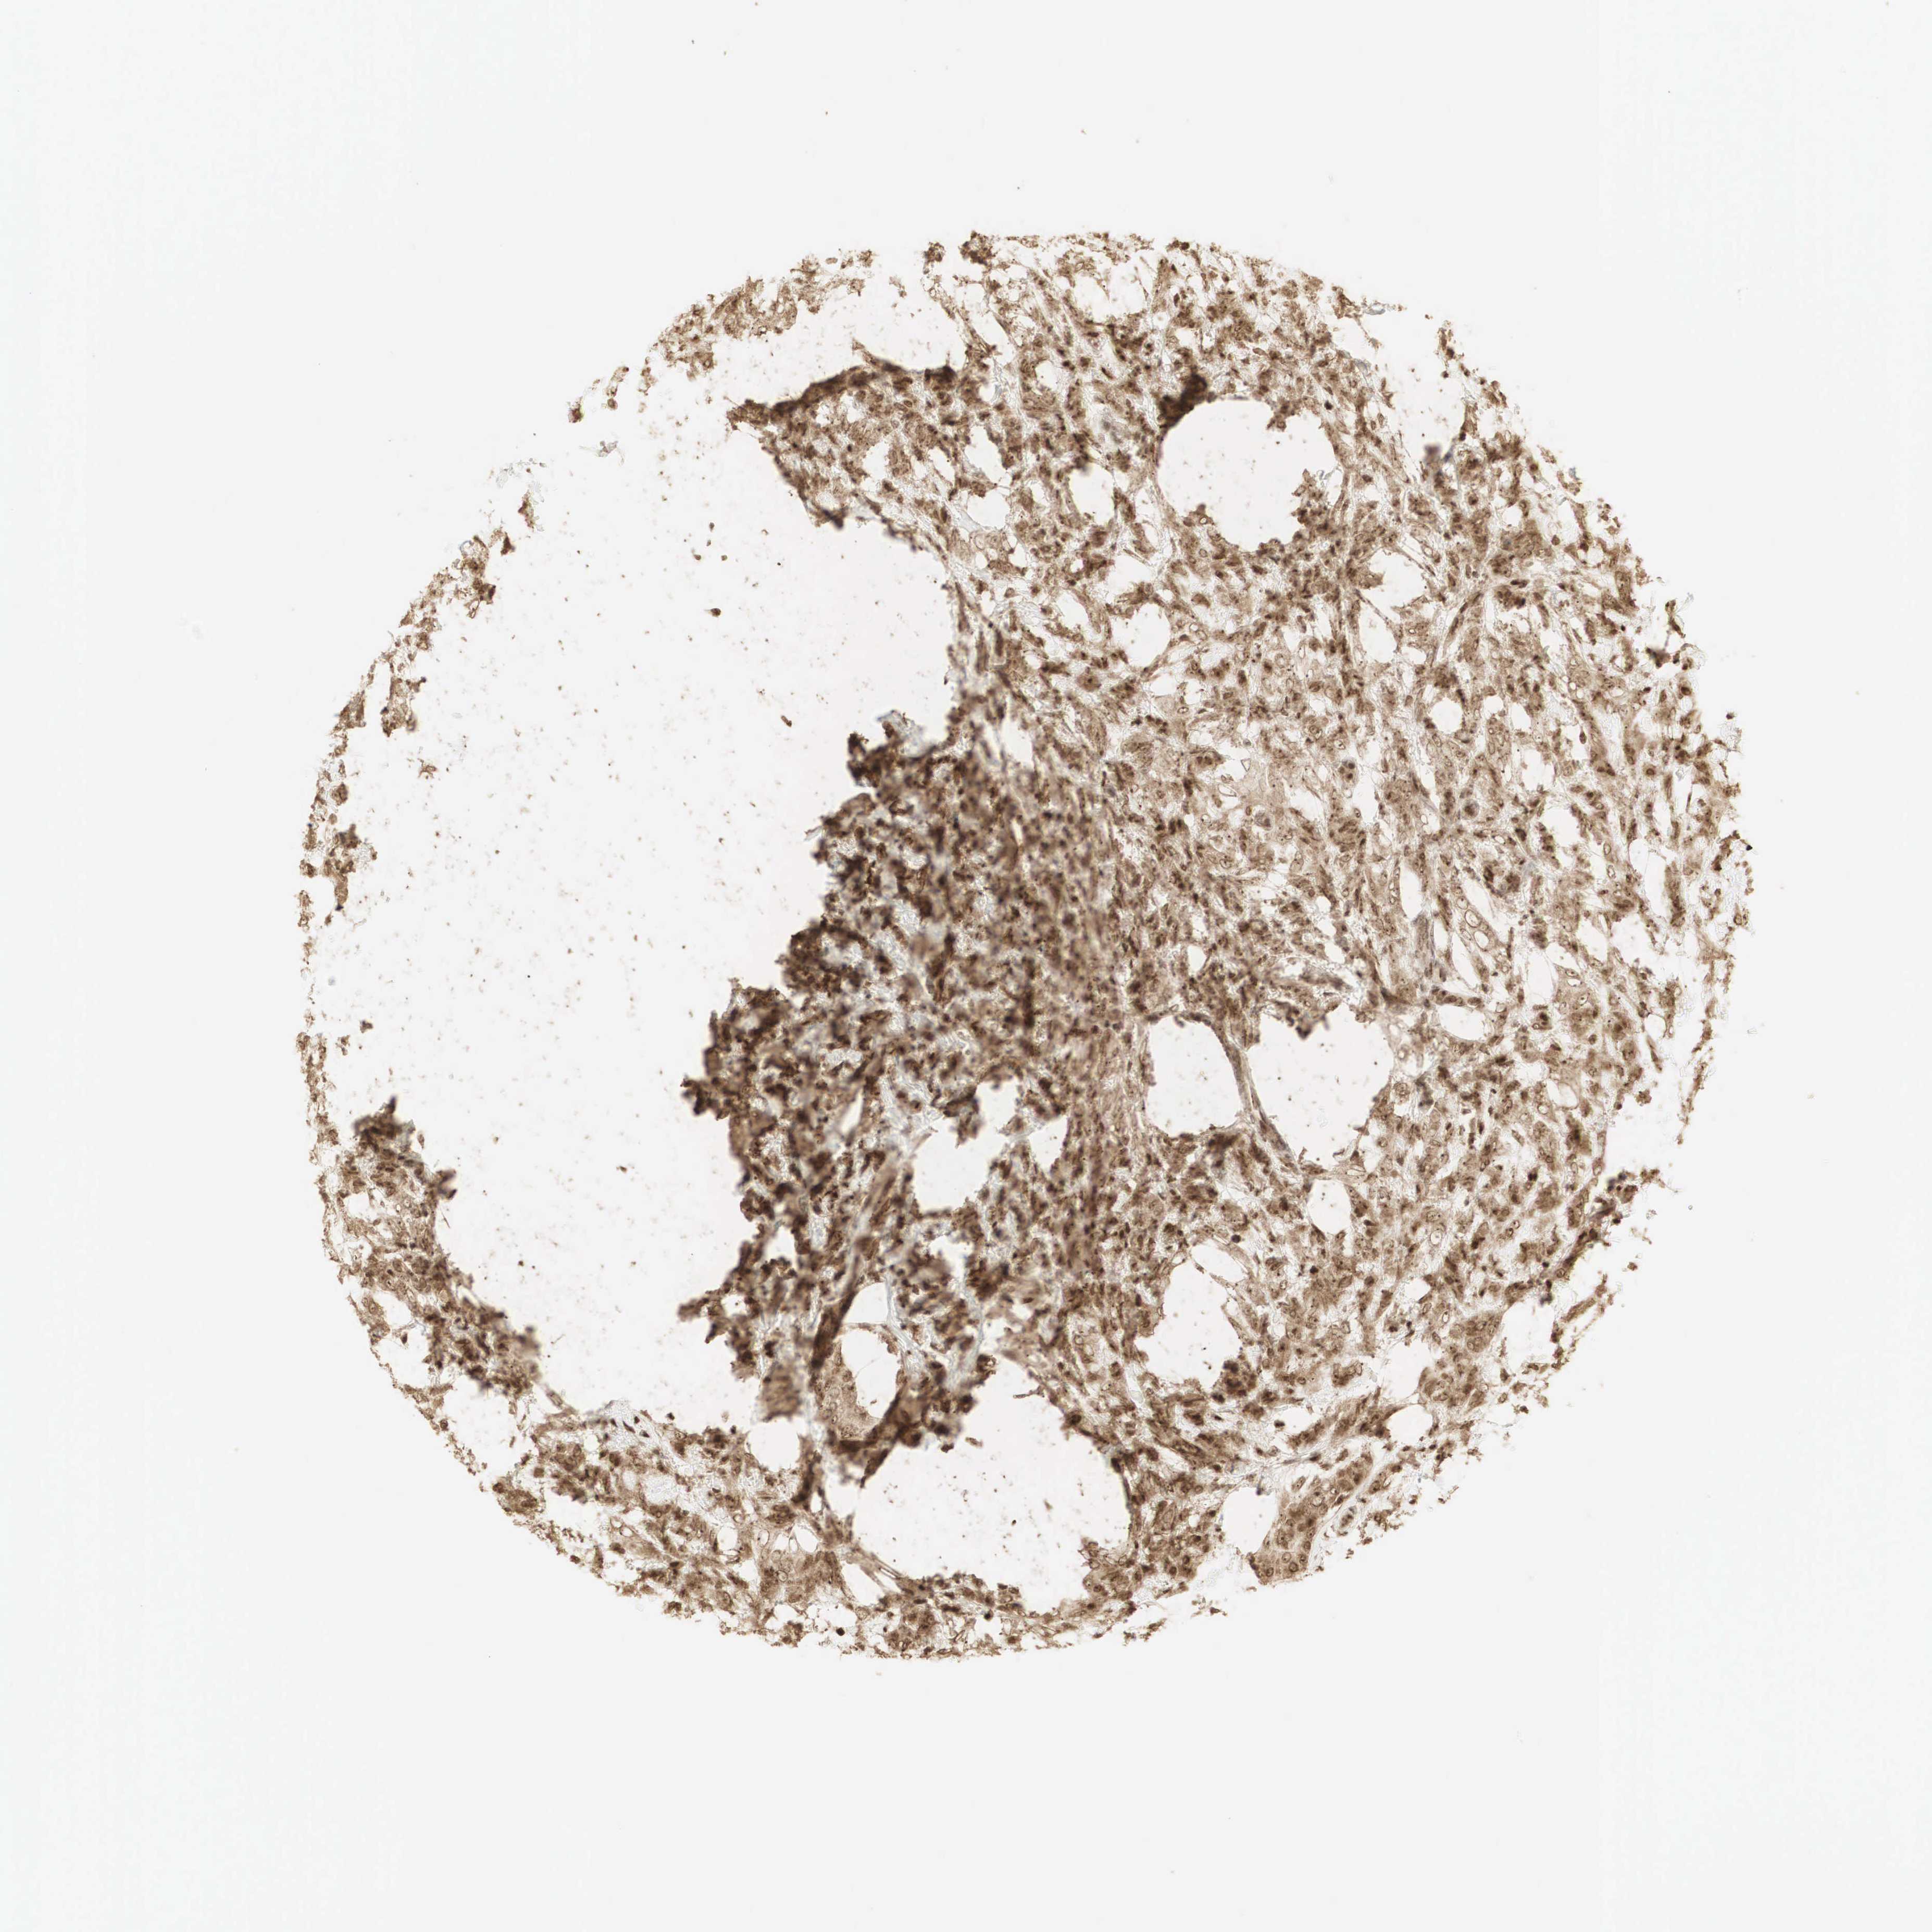

CANCER BREAST CANCER Show tissue menu

BRCA TCGA BRCA VALIDATION PROTEIN EXPRESSION

Breast cancer

Human cancer

Breast invasive carcinoma